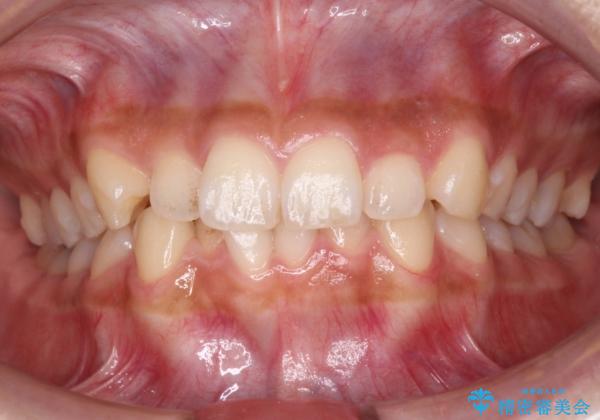

犬歯のねじれ 下の歯のがたがた インビザラインで

- 右上の犬歯のねじれ、下の歯のがたつきを主訴に来院。

インビザラインで歯を抜かずに並べました。

初回:上顎16ステージ 下顎22ステージ

リファインメント: 上顎23ステージ 下顎20ステージ

下の前歯のがたがたがそれなりにあったため、リファインメントを行いました。